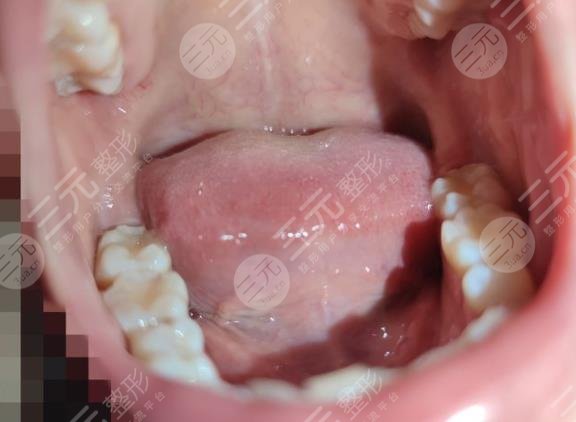

Wuhan University Stomatological Hospital found that it is really better, and the diagnosis and treatment environment is particularly comfortable, the doctor gave me a detailed examination, told me that the gums have been inflamed, let me repair in time, for my teeth to clean up before starting to repair, at the beginning of the cleaning to me used a certain amount of medicine, at that time there was not so much pain, go home to rest for about a day, and then let me go to the hospital to repair again, a total of three times, my teeth were repaired.

Now it has been almost two months since the restoration was completed, and the overall result is really clear, I didn't expect that after such a tooth restoration, eating will not be affected, and there will be no pain, I am really grateful to the doctors of Wuhan University Stomatological Hospital.